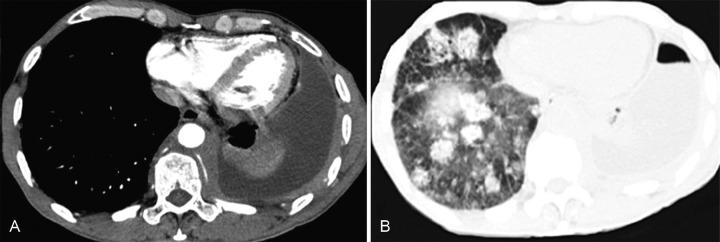

Primary lung lymphoma is a rare entity accounting for approximately 0.3% of all primary neoplasia of the lung and includes diffuse large B-cell lymphoma (DLBL) and lymphomatoid granulomatosis (LYG). Considering that clinical features may be similar, whereas epidemiology, morphology, and radiological features are different, the authors report a case of a middle-aged man who presented multiple pulmonary nodules in the lower lobes and ground-glass opacities scattered bilaterally on computed tomography. Clinically, he presented a consumptive syndrome with respiratory failure and pleurisy, which progressed until death. The autopsy findings were consistent with lymphomatoid granulomatosis (LYG) grade 3/ diffuse large B-cell lymphoma (DLBL). The authors call attention to the difficulty of establishing an accurate diagnosis, mainly when the demonstration of EBV-infected atypical B-cells fails.

原发性肺淋巴瘤是一种罕见的疾病,约占所有原发性肺肿瘤的0.3%,包括弥漫性大B细胞淋巴瘤(DLBL)和淋巴瘤样肉芽肿病(LYG)。鉴于临床特征可能相似,而流行病学、形态学和放射学特征不同,作者报告了一例中年男性病例,该患者在计算机断层扫描中显示下叶有多个肺结节,双侧散在磨玻璃影。临床上,他表现为消耗综合征伴呼吸衰竭和胸膜炎,病情进展直至死亡。尸检结果符合3级淋巴瘤样肉芽肿病(LYG)/弥漫性大B细胞淋巴瘤(DLBL)。作者提醒注意准确诊断的困难,主要是在未能证实EBV感染的非典型B细胞时。